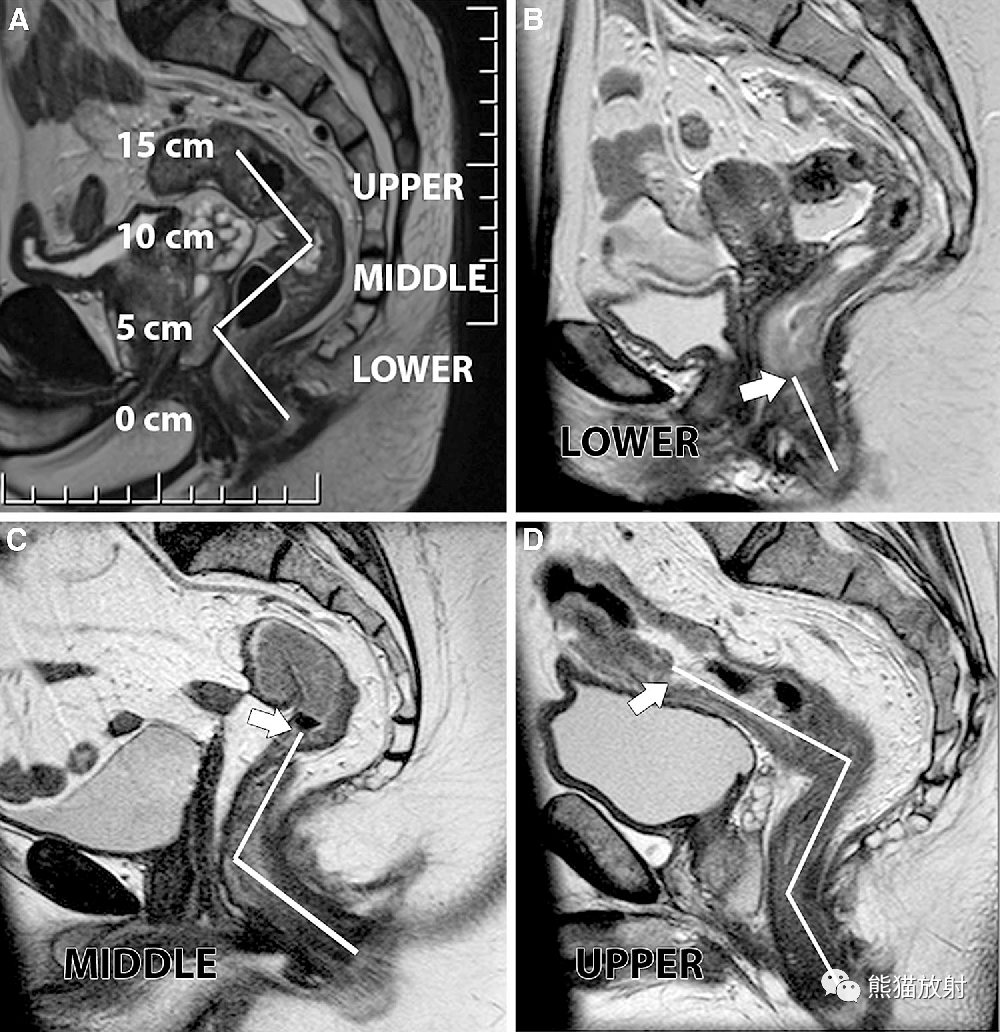

图a:直肠从肛管延伸至直肠乙状结肠交界处约15cm,分为下段(0-5cm),中